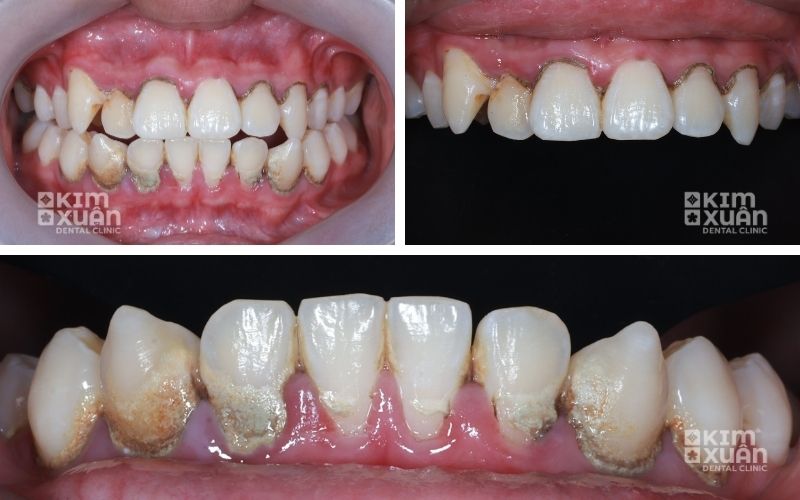

3. Dấu Hiệu Nhận Biết Viêm Nướu Răng (Viêm Lợi)

Viêm nướu răng thường không gây đau rõ rệt, nên rất dễ bị bỏ qua. Người bệnh nên cảnh giác nếu xuất hiện các dấu hiệu sau:

Nướu sưng, mềm, đỏ sẫm hoặc đỏ tím, sưng hơn bình thường

Chảy máu chân răng khi đánh răng hoặc dùng chỉ nha khoa

Hơi thở có mùi hôi kéo dài do vi khuẩn phát triển

Cảm giác khó chịu, ê nhẹ, ngứa hoặc rát ở nướu

Nướu nhạy cảm hơn bình thường khi chạm vào hoặc khi ăn nhai